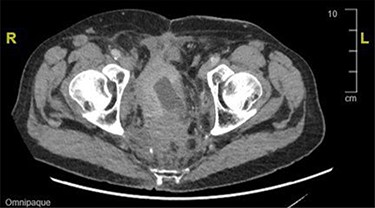

During an admission for deep vein thrombosis post lithotripsy of urethral calculi, a computed tomography (CT) of the thorax, abdomen and pelvis showed an extensive mass in the presacral region with invasion of the urinary bladder and orifices of both ureters with enlarged lower paraaortic and pelvic lymph nodes (Fig. 1). A urinary bladder biopsy obtained during a rigid cystoscopy showed an indeterminate invasive carcinoma.

CT image showing an extensive mass in the presacral region with invasion to the urinary bladder and both ureters.